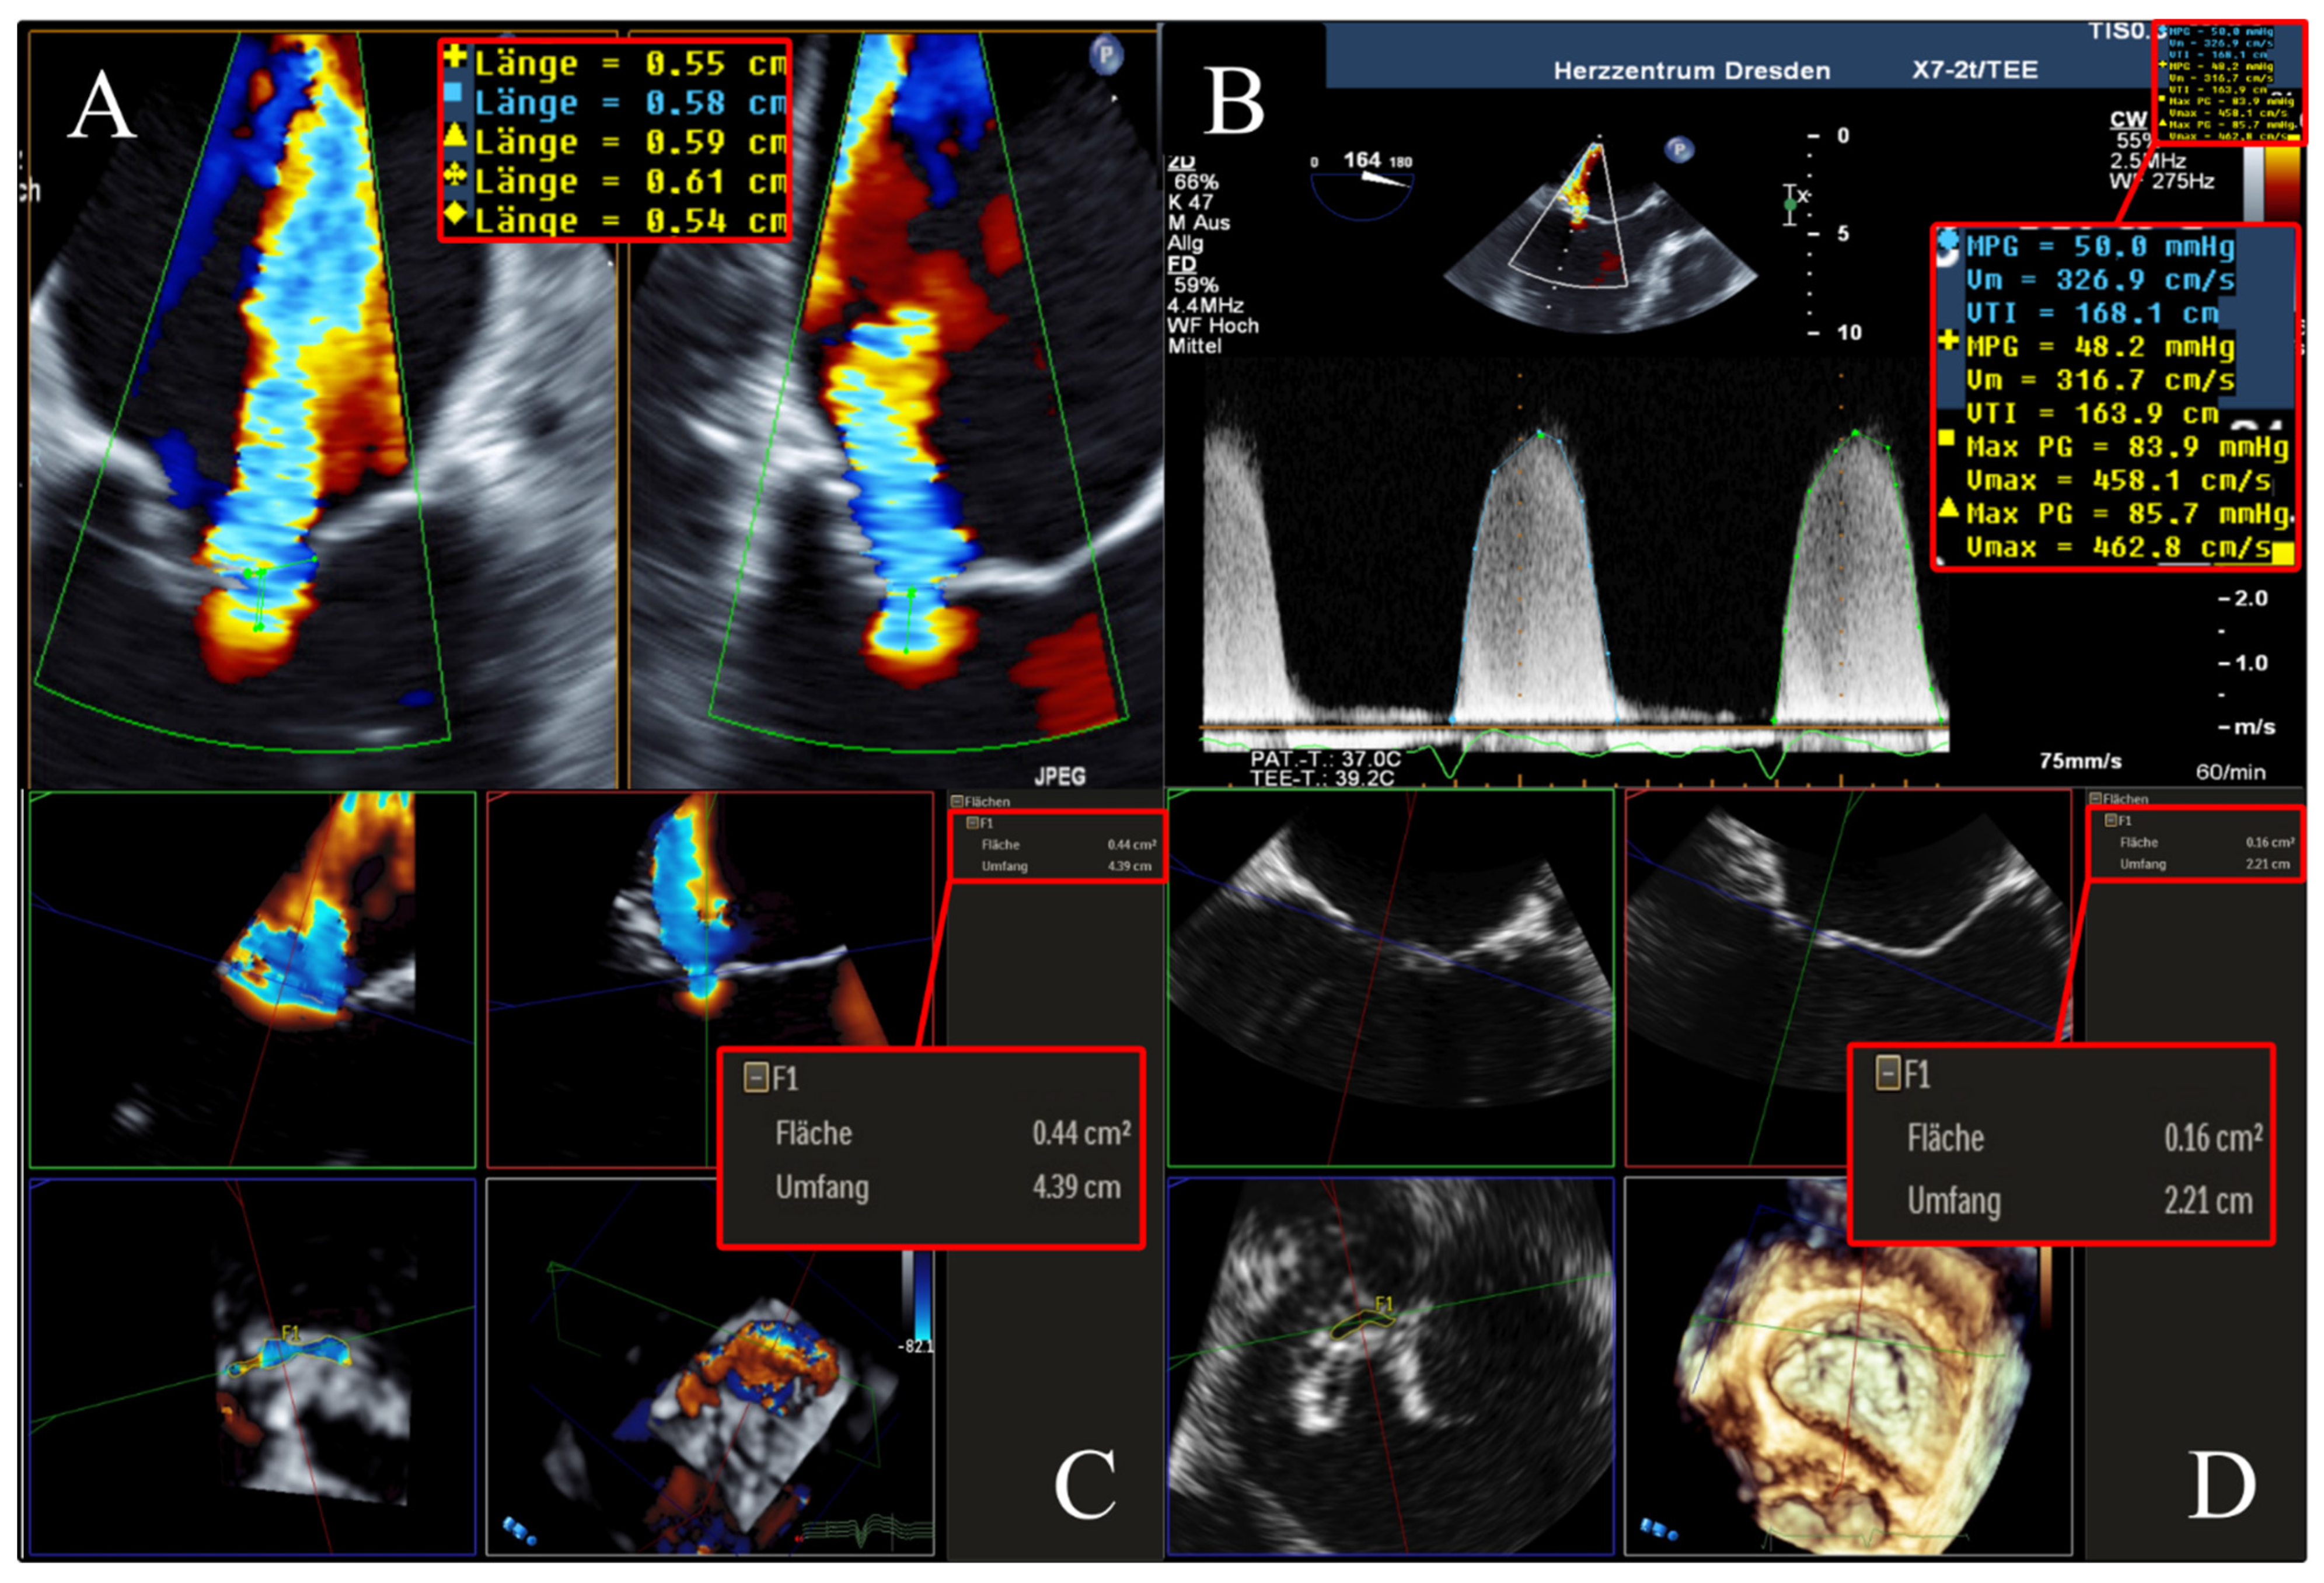

To determine the EROA using 2D PISA, biplane 2D color Doppler images (X-Plane views) were acquired optimally at a Nyquist velocity between 20 and 45 m/s. In the TEE 4-chamber view as well as in the orthogonal section plane with maximal expression of proximal convergence, the radius of proximal convergence between color change and plane of coaptation defect (minimal regurgitation area) was measured in mid-systole over different heartbeats. In addition, the maximum regurgitation velocity (MR-Vmax) and velocity–time integral (MR-VTI) in systolic phase of CW Doppler recordings were determined (Figure 2). Using the PISA method, the EROA was calculated according to the recommendations of the European Association of Cardiovascular Imaging (EACVI) [2].

Figure 2. Determination of 2D PISA in biplane 2D color Doppler dataset and CW Doppler dataset. Echocardiographic images with 2 orthogonal slice planes of the 2D color Doppler dataset (mid-systolic) with Nyquist velocity of 38.5 cm/s (left); determination of PISA radius in 2 planes (diameters with crosses), MR-VTI (dotted outline), and MR-Vmax in the CW Doppler dataset (right) for calculation of regurgitation area. Abbreviations: 2D = two-dimensional; PISA = proximal isovelocity surface area; CW = continuous wave; MR-VTI = mitral regurgitation velocity–time integral; MR-Vmax = maximum mitral regurgitation velocity.

To facilitate a better understanding of our subsequent results of the cross-method comparisons, we illustrate in Figure 5 a representative example of the same patient evaluated for FMR using the 3D VCA, AROA, and EROA 2D PISA.

Figure 5. Example of a 51-year-old, male patient suffering from FMR due to non-ischemic dilated cardiomyopathy. (A,B) ERO quantified using 2D PISA method was 0.20 cm2, with a mean MR-Vmax of 460 cm/s. (C) 3D VCA derived by multiplanar reconstruction in a 3D color Doppler dataset was 0.44 cm2. (D) AROA derived by multiplanar reconstruction in a 3D Doppler dataset without color was 0.16 cm2. Abbreviations: FMR = functional mitral valve regurgitation; 2D = two-dimensional; PISA = proximal isovelocity surface area; CW = continuous wave; MR-Vmax = maximum mitral regurgitation velocity; 3D = three-dimensional; VCA = vena contracta area; AROA = anatomical regurgitation orifice area.